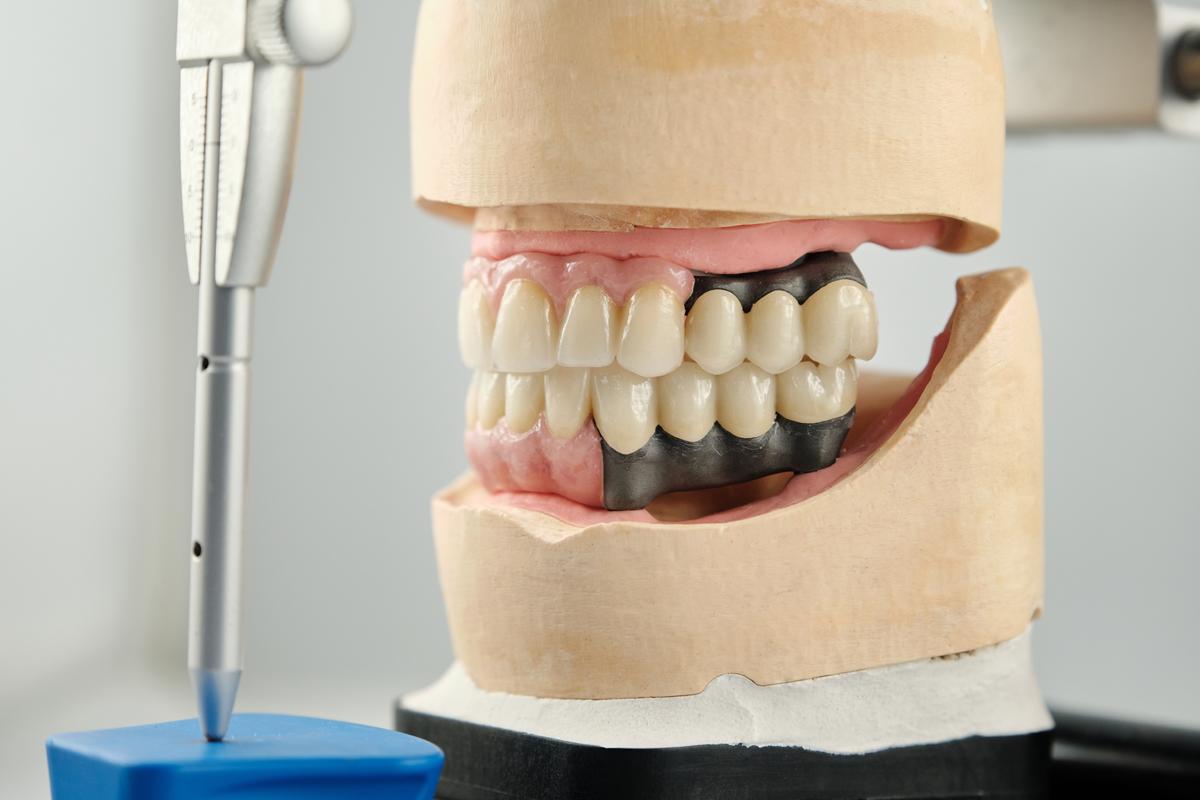

Un dentiste spécialisé en implantologie est un dentiste qui a suivi une formation supplémentaire pour acquérir les compétences et les connaissances nécessaires à la pose d’implants dentaires. Les implants dentaires sont des prothèses dentaires qui sont insérées dans la mâchoire pour remplacer les racines des dents manquantes. Les implants dentaires peuvent être utilisés pour remplacer une ou plusieurs dents, ou même pour soutenir des prothèses dentaires amovibles.

Pour devenir un dentiste spécialisé en implantologie, il est nécessaire de suivre une formation supplémentaire après l’obtention du diplôme en médecine dentaire. Cette formation peut varier en fonction de la région et des exigences légales. Dans la plupart des cas, les dentistes doivent suivre un programme de formation spécialisé et effectuer un certain nombre de cas sous supervision avant de pouvoir pratiquer l’implantologie de manière autonome.

Les dentistes spécialisés en implantologie doivent également avoir une connaissance approfondie de l’anatomie de la mâchoire et des tissus environnants. Ils doivent être capables de planifier et d’exécuter des procédures d’implantation complexes, et doivent aussi être en mesure de gérer les complications qui peuvent survenir lors de la pose d’implants dentaires.